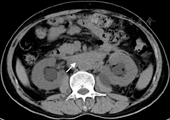

患者男性,50岁。因胫前水肿5个月,左肾盂积水2个月于2014年10月15日收入我院肾内科。2014年5月患者无明显诱因出现双侧胫前可凹陷性水肿,晨轻暮重,伴乏力、活动耐量减低、双下肢肌肉酸胀感,无眼睑、颜面部水肿,无肉眼血尿、泡沫尿,无头痛、咽痛、发热、皮疹、关节痛等不适。当地诊所查尿常规:比重1.010,尿蛋白阴性,潜血阴性;血肌酐(SCr) 104 μmol/L。2014年8月出现食欲减退、恶心等不适,复查SCr 150 μmol/L,当地诊所予健胃消食的中成药治疗。2014年10月就诊我院门诊,血压110/85 mmHg(1 mmHg=0.133 kPa);查血常规:WBC 5.05×109/L,中性粒细胞百分比58.5%,嗜酸性粒细胞0.03×109/L,Hb 102 g/L,PLT 244×109/L;尿常规:比重1.006,尿蛋白阴性,潜血5.3红细胞/μl,WBC 2.6细胞/μl;24 h尿蛋白0.627 g; SCr 345.9 μmol/L。超声提示左肾包膜下可疑积液,范围0.6 cm×4.4 cm;双肾集合系统分离,左侧宽约2.3 cm,右侧宽约2.6 cm。胸腹盆CT平扫(图1):腹膜后软组织密度影,包绕腹主动脉、下腔静脉及双侧髂总动静脉,考虑腹膜后纤维化(retroperitoneal fibrosis, RPF)可能,双侧肾盂肾盏扩张积水。核素肾血流图:左肾血流灌注显著减低,滤过功能严重受损;右肾血流灌注略减低,滤过功能中度受损。GFR 37.5 ml/min,右肾GFR为22.3 ml/min,左肾GFR为15.2 ml/min。